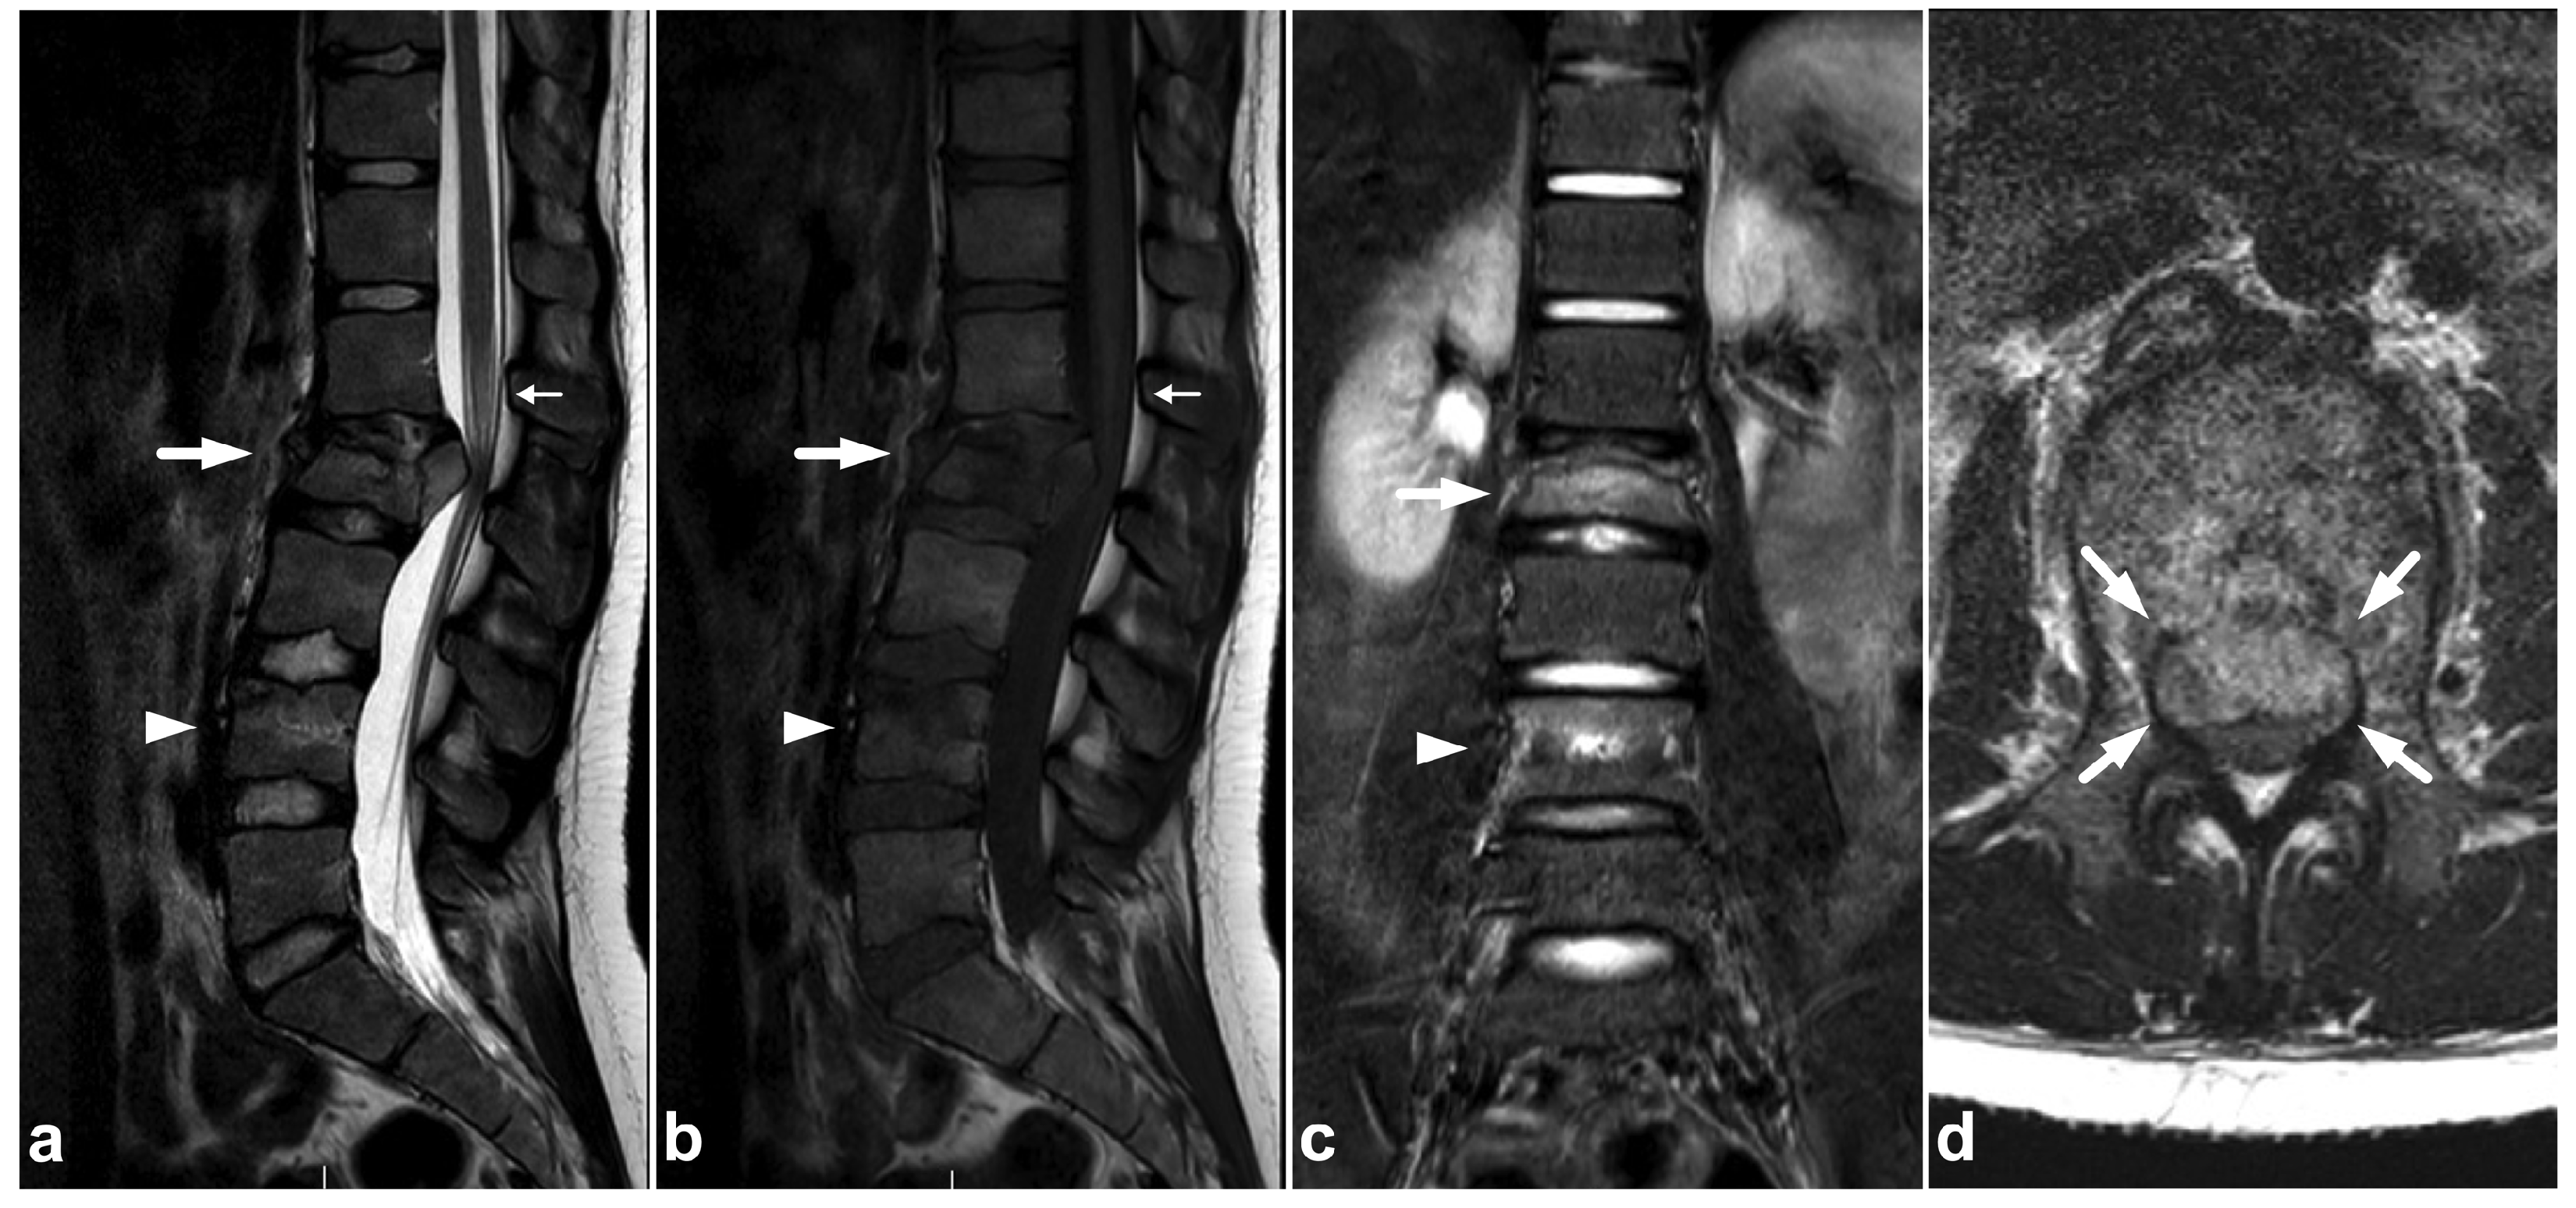

Figure 2.

(a) Sagittal T2-weighted. (b) Sagittal T1-weighted. (c) Sagittal STIR. (d) Axial T2-weighted. A 16-year-old female, back pain after falling down the stairs. Burst fracture in L2 (arrow) with a fragment protruding into the spinal canal and compressing the conus medullaris. Edema can be seen in the conus medullaris immediately above the most compressed level (small arrow). In L4, there is a stable compression fracture (arrowheads). No intraspinal hematoma can be seen. Minor paraspinal edema/hematoma is best demonstrated in the axial image (d).